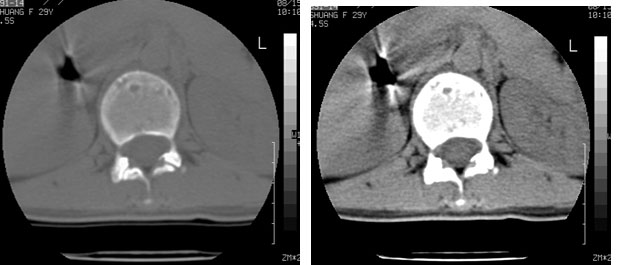

标题: CT10087:女,29岁,多发肿瘤样病变。 [打印本页]

标题: CT10087:女,29岁,多发肿瘤样病变。

车祸致t12压缩性骨折,行ct扫描意外发现椎体多发肿瘤样病变,建议加拍骨盆平片,患者平常无症状。

考虑多发骨髓瘤可能性大。(骨松质内弥漫性分布,边缘清晰的溶骨性破坏,无硬化。睥脏增大,其内有多个圆形底密度影。淋巴瘤不除。

椎体多发性溶骨性破坏,部分融合,椎旁无软组织肿块、椎间隙正常,t12 压缩,脾脏增大,其内示多发低密度影,首先考虑多发性骨髓瘤。病人较年轻,平素无异常,转移瘤可能性小。